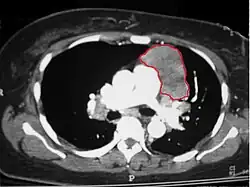

When a thymoma is suspected, a CT/CAT scan is generally performed to estimate the size and extent of the tumor, and the lesion is sampled with a CT-guided needle biopsy. Increased vascular enhancement on CT scans can be indicative of malignancy, as can be pleural deposits.[2] Limited biopsies are associated with a very small risk of pneumomediastinum or mediastinitis and an even-lower risk of damaging the heart or large blood vessels. Sometimes thymoma metastasize for instance to the abdomen.[6]

Gallery

-

An encapsulated cystic thymoma. -